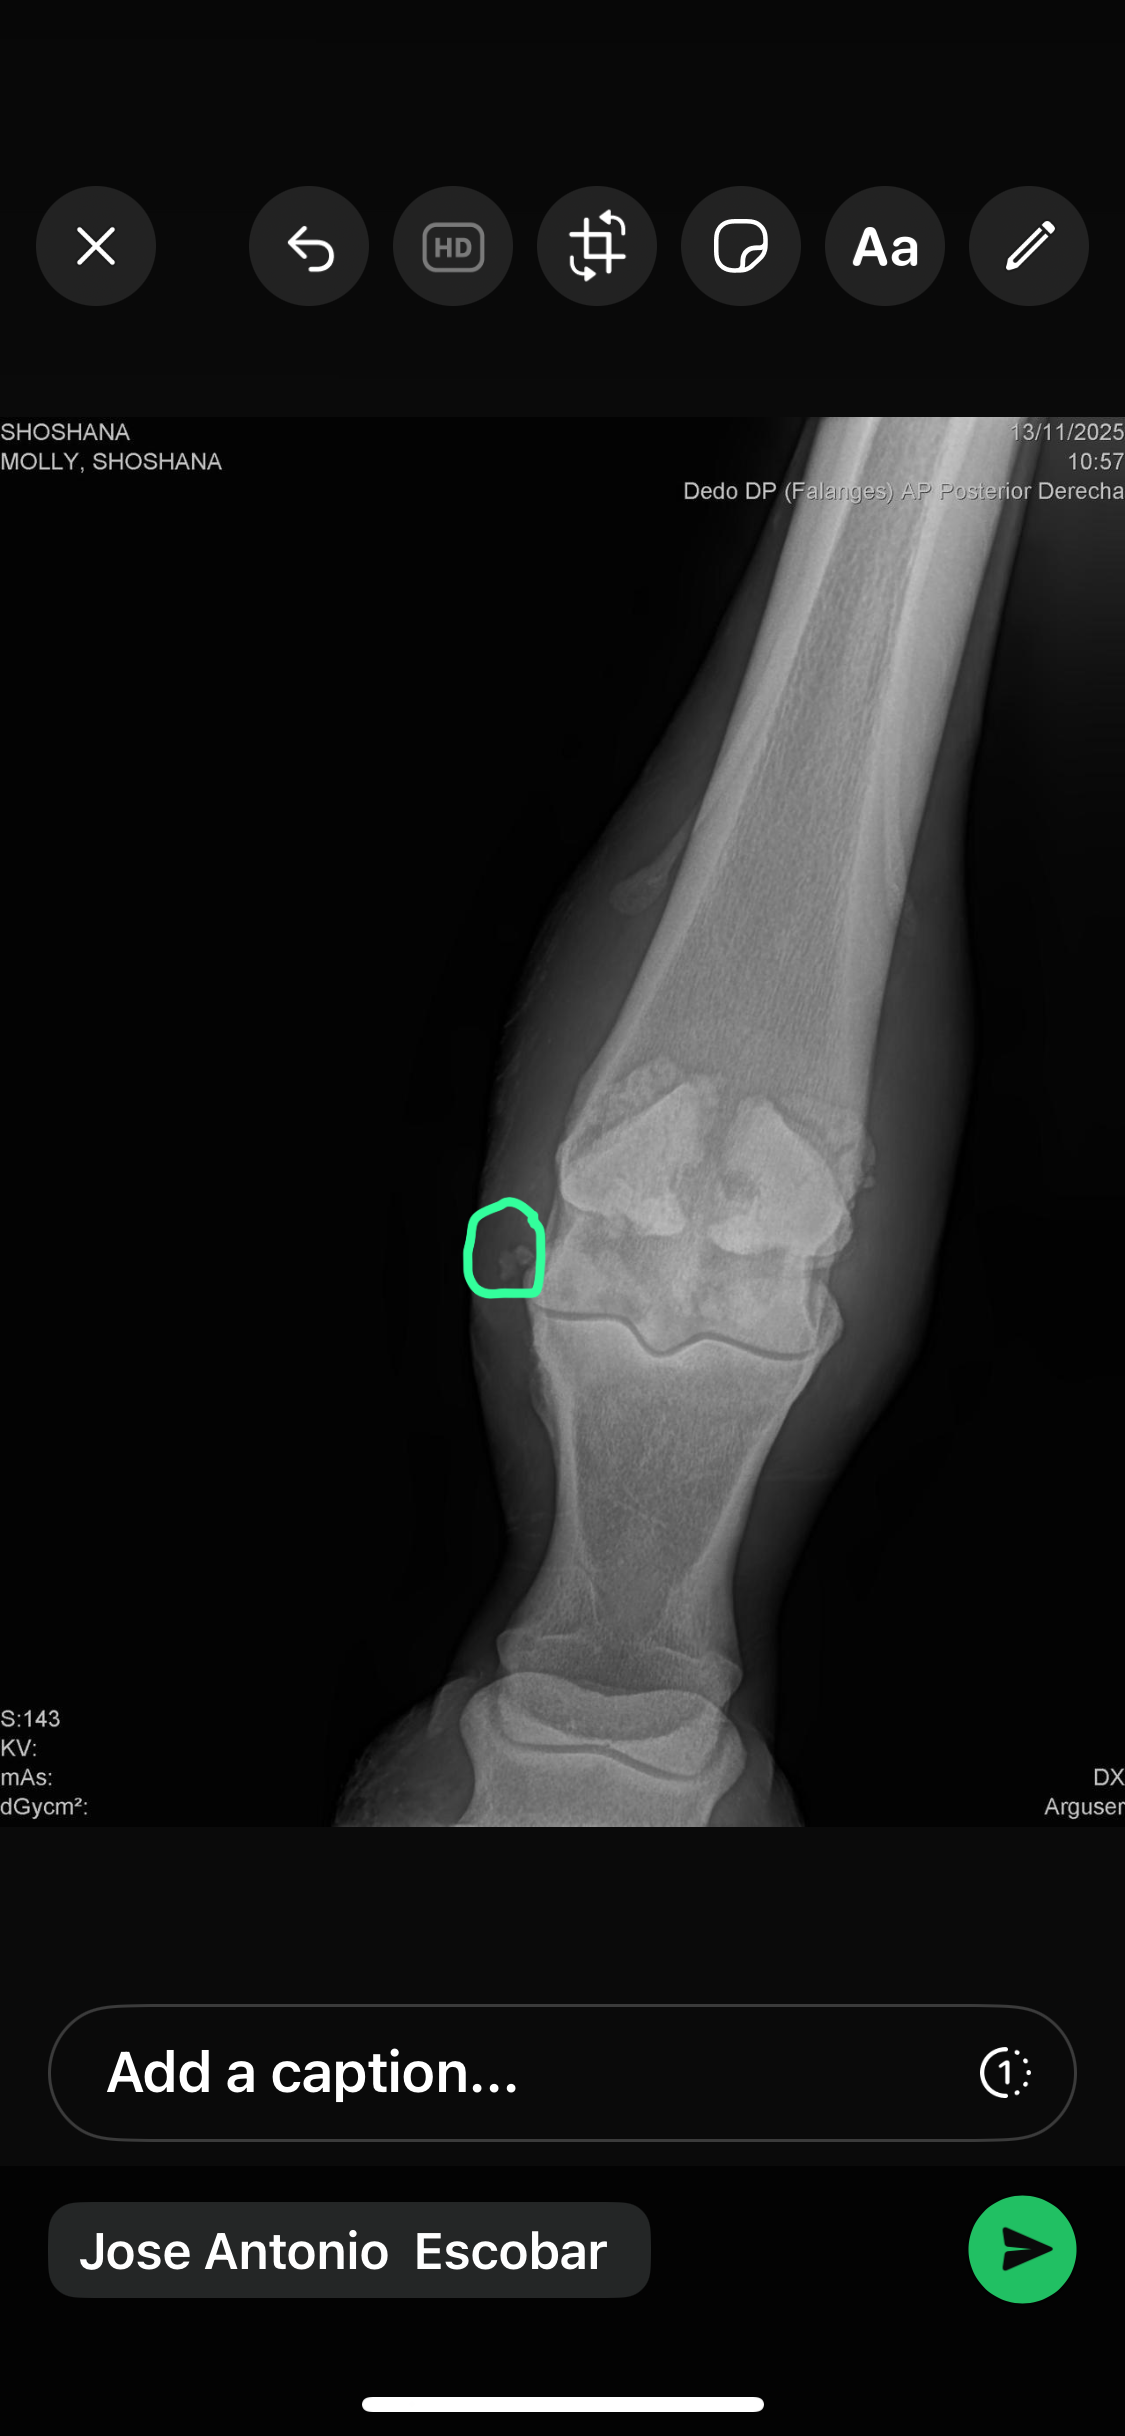

As she began her recovery, the reason for her abandonment slowly became clear. Shoshana has equine OCD (osteochondritis dissecans) — a serious yet treatable joint condition that has caused a piece of bone to fragment and float within her joint. This fragment has now caused a painful joint infection, putting her at significant medical risk.

Just a few days ago, Shoshana suffered a new and serious injury. While running in the field, she likely slipped, tearing the sesamoid ligaments at the back of her hock. This has caused the sesamoid bone to become displaced, adding severe pain and instability to an already fragile situation.

• Her OCD is chronic and will require surgery to resolve it

• The torn ligaments and displaced sesamoid bone also require surgical intervention